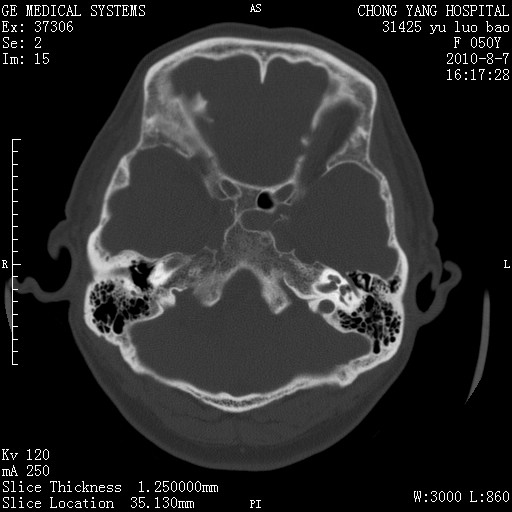

标题: CT28285:听力下降一年,头昏。 [打印本页]

标题: CT28285:听力下降一年,头昏。

右侧桥小脑角去等密度占位,右侧内听道扩大、骨质吸收,考虑:右侧听神经瘤,建议增强检查。

右侧内听道扩大、骨质吸收,中脑受压左移,考虑:右侧听神经瘤,建议增强检查。支持!

骨窗示右侧内听道扩大,考虑右侧听神经瘤。

右侧桥小脑角区等密度占位,内耳道扩大,听神经瘤